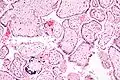

ساختار

در تشکیل جفت بافتهای خارج جنینی و بافت آستر رحم (آندومتر) مادر نقش دارد. بعد از تکمیل عمل لانهگزینی، لایهٔ تروفوبلاستی به دو قسمت تمایز پیدا میکند:

- ۱)لایهٔ داخلی (سیتو تروفوبلاست)

- ۲)لایهٔ خارجی (سینسیتیو تروفوبلاست) حفرهها در تروفوبلاست ایجاد میشود، بلافاصله از خون مادری پر میشوند. سلولهای بافت آستر رحم تغییراتی پیدا میکنند که واکنش دیستی دوالی گفته میشود که این عملشان در پاسخ به هجوم تروفوبلاست انجام میگیرد. در داخل سلولها گلیکوژن و لیپید جمع میشود.